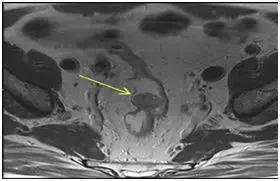

7、 直肠神经内分泌瘤需要做CT/MRI么?

答:由于直肠神经内分瘤仍是低度恶性的肿瘤,即使不足1cm的肿瘤,也有2-3%的可能性发生转移,主要是肠周、盆腔淋巴结和肝脏,因此原则上建议做腹CT和盆腔MRI或CT,排除转移。

本图截取于国外文献